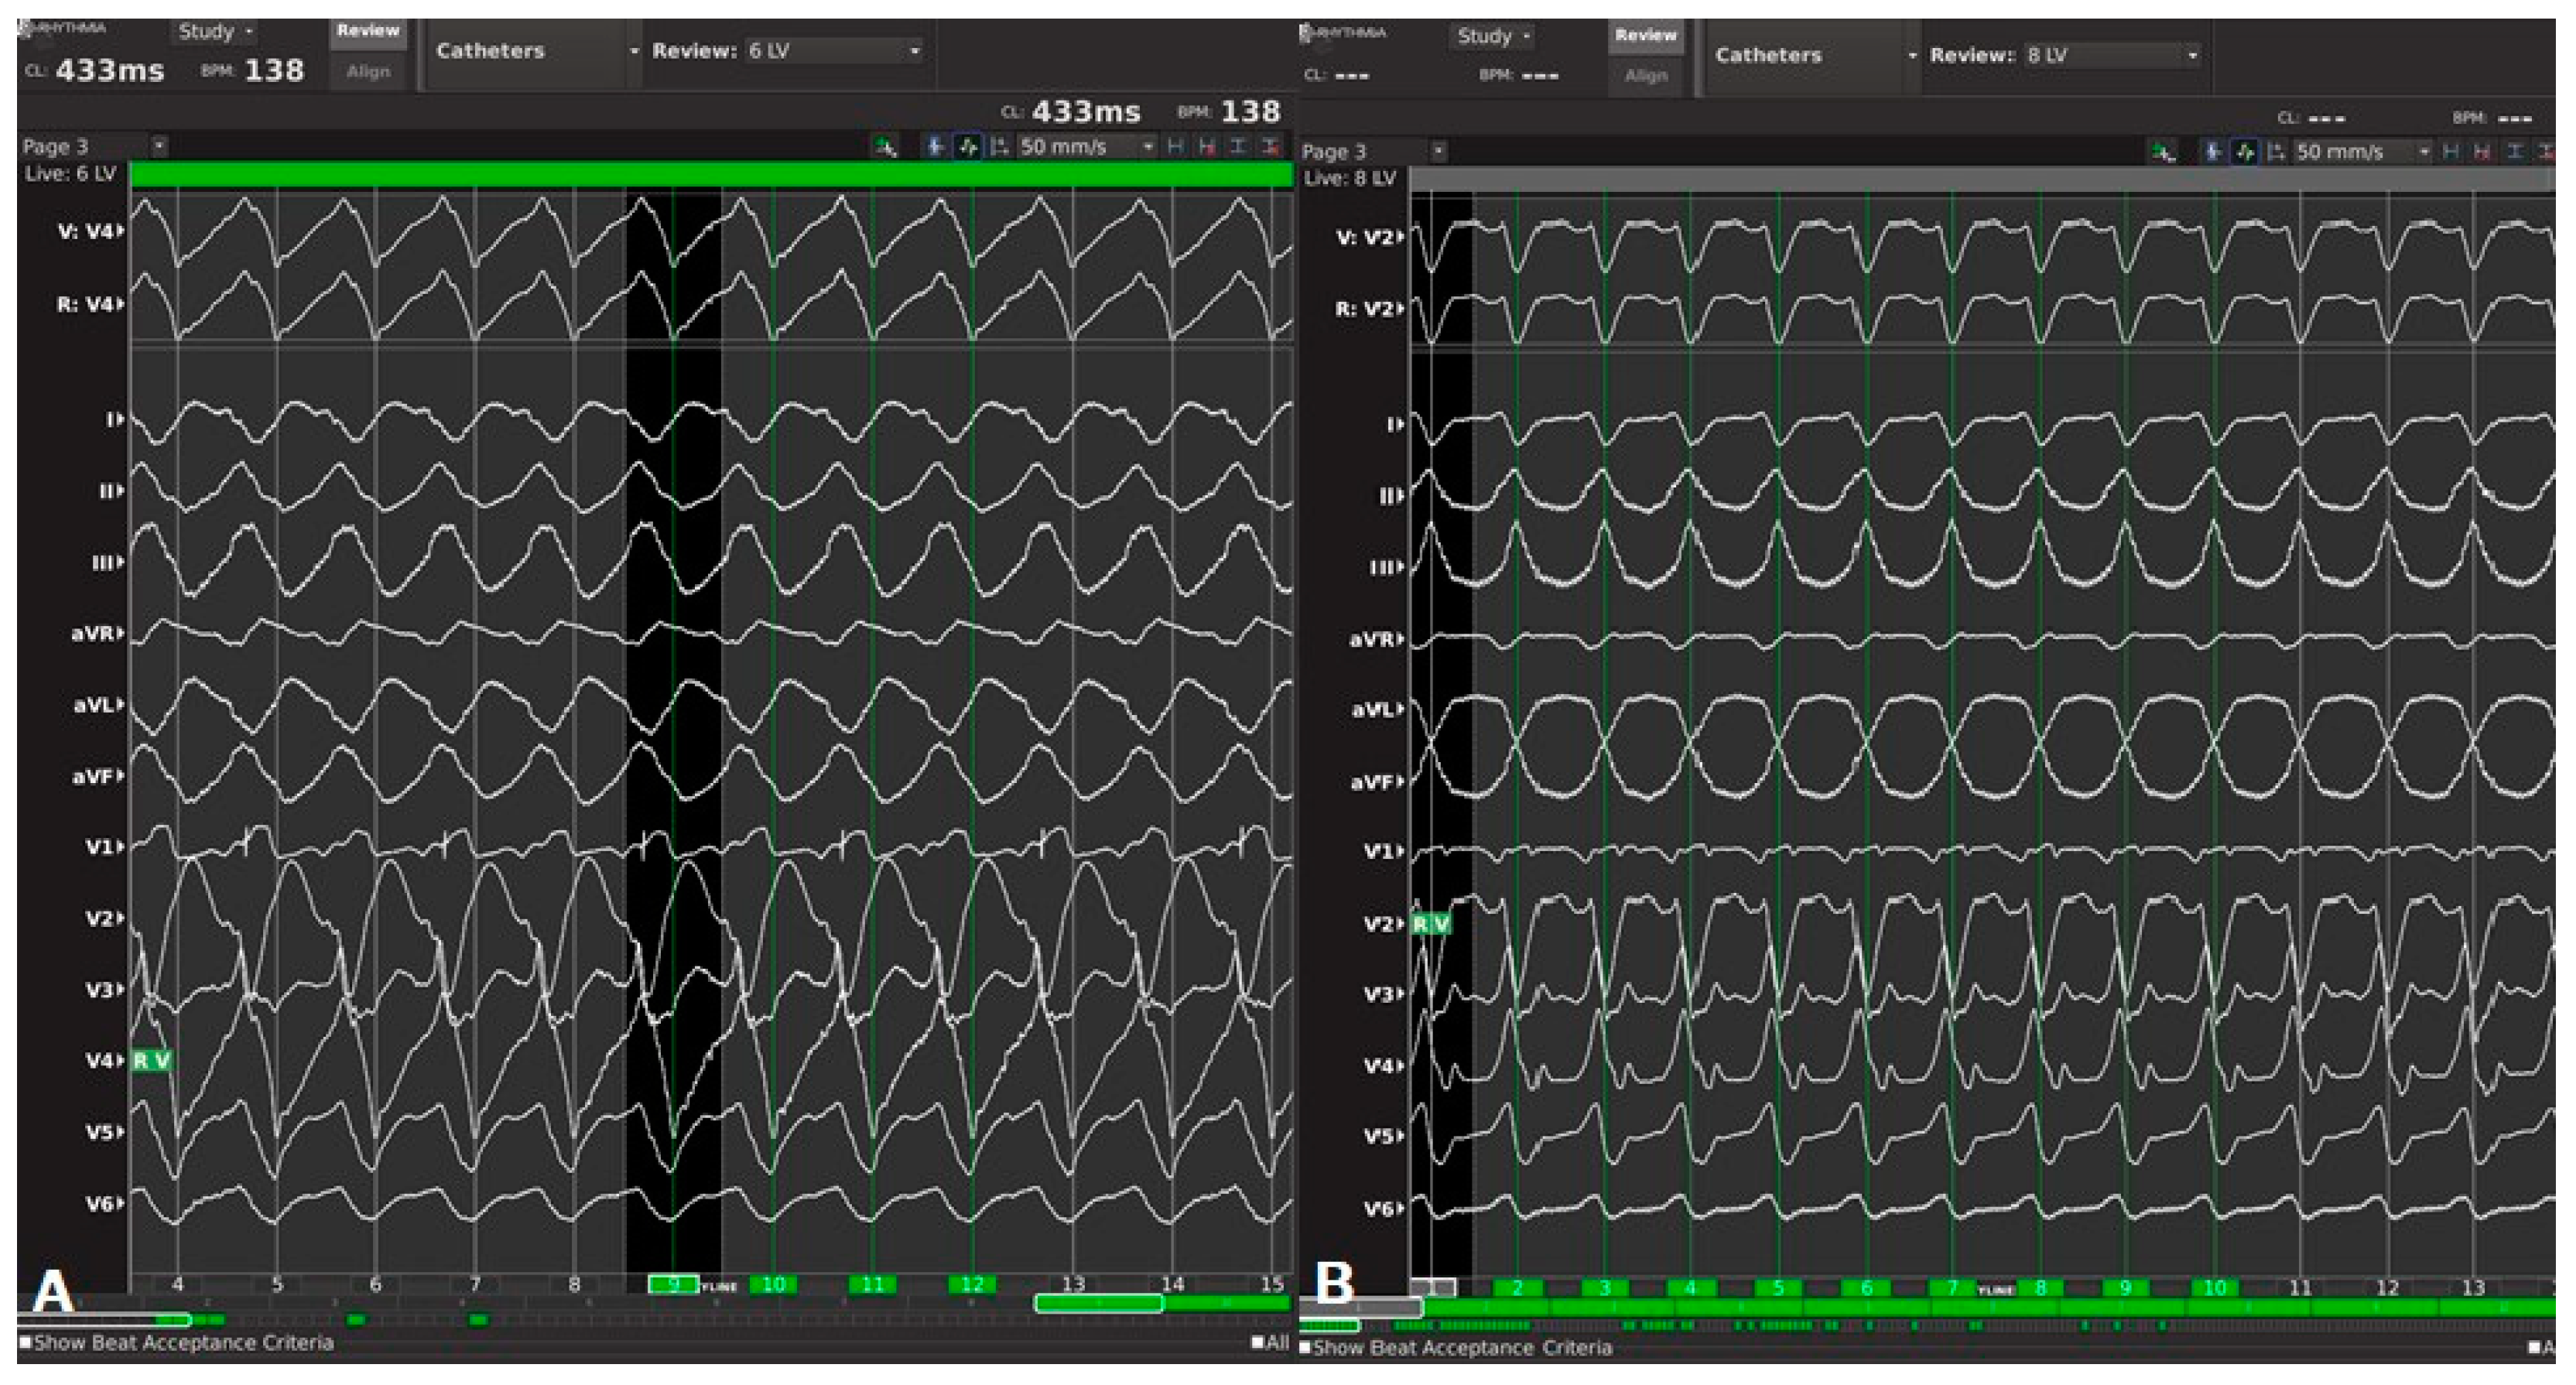

4. Case Description of the ECMO Supported Ablation